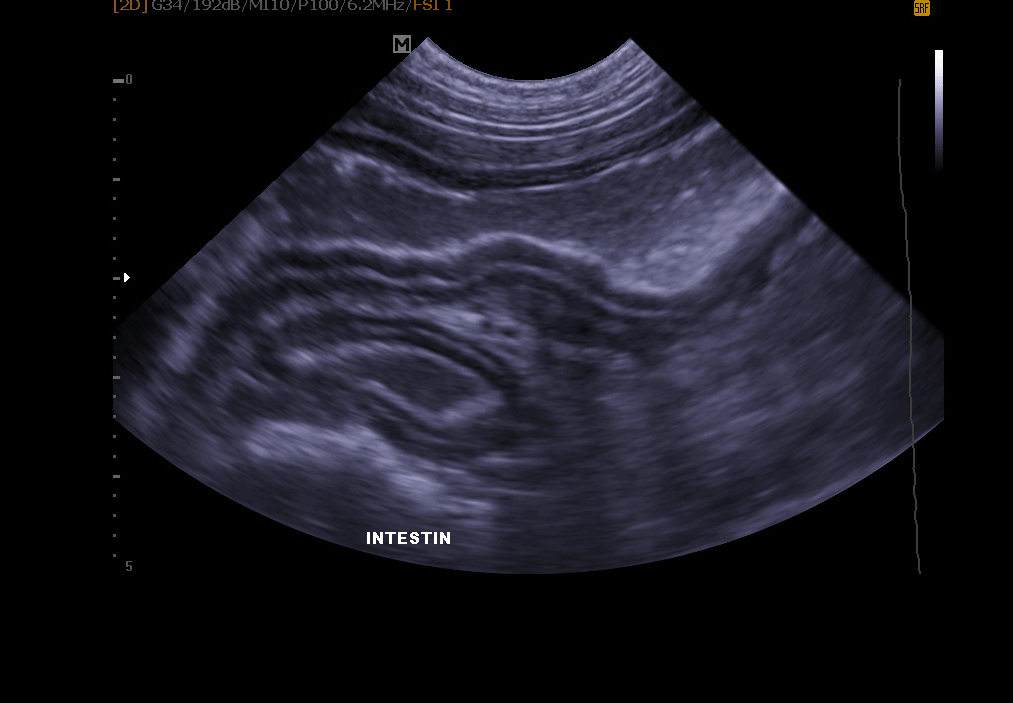

Echographie abdominale: elle permet l’exploration de le vessie (recherche de calculs, polypes, tumeur), des reins, de la rate , du foie , du pancréas et autres organes abdominaux.

Examen de l’appareil génital: infection de l’utérus, gestation détectable dés 18 à 21 jours chez la chatte et la chienne, kystes ovariens, exploration de la prostate chez le mâle.